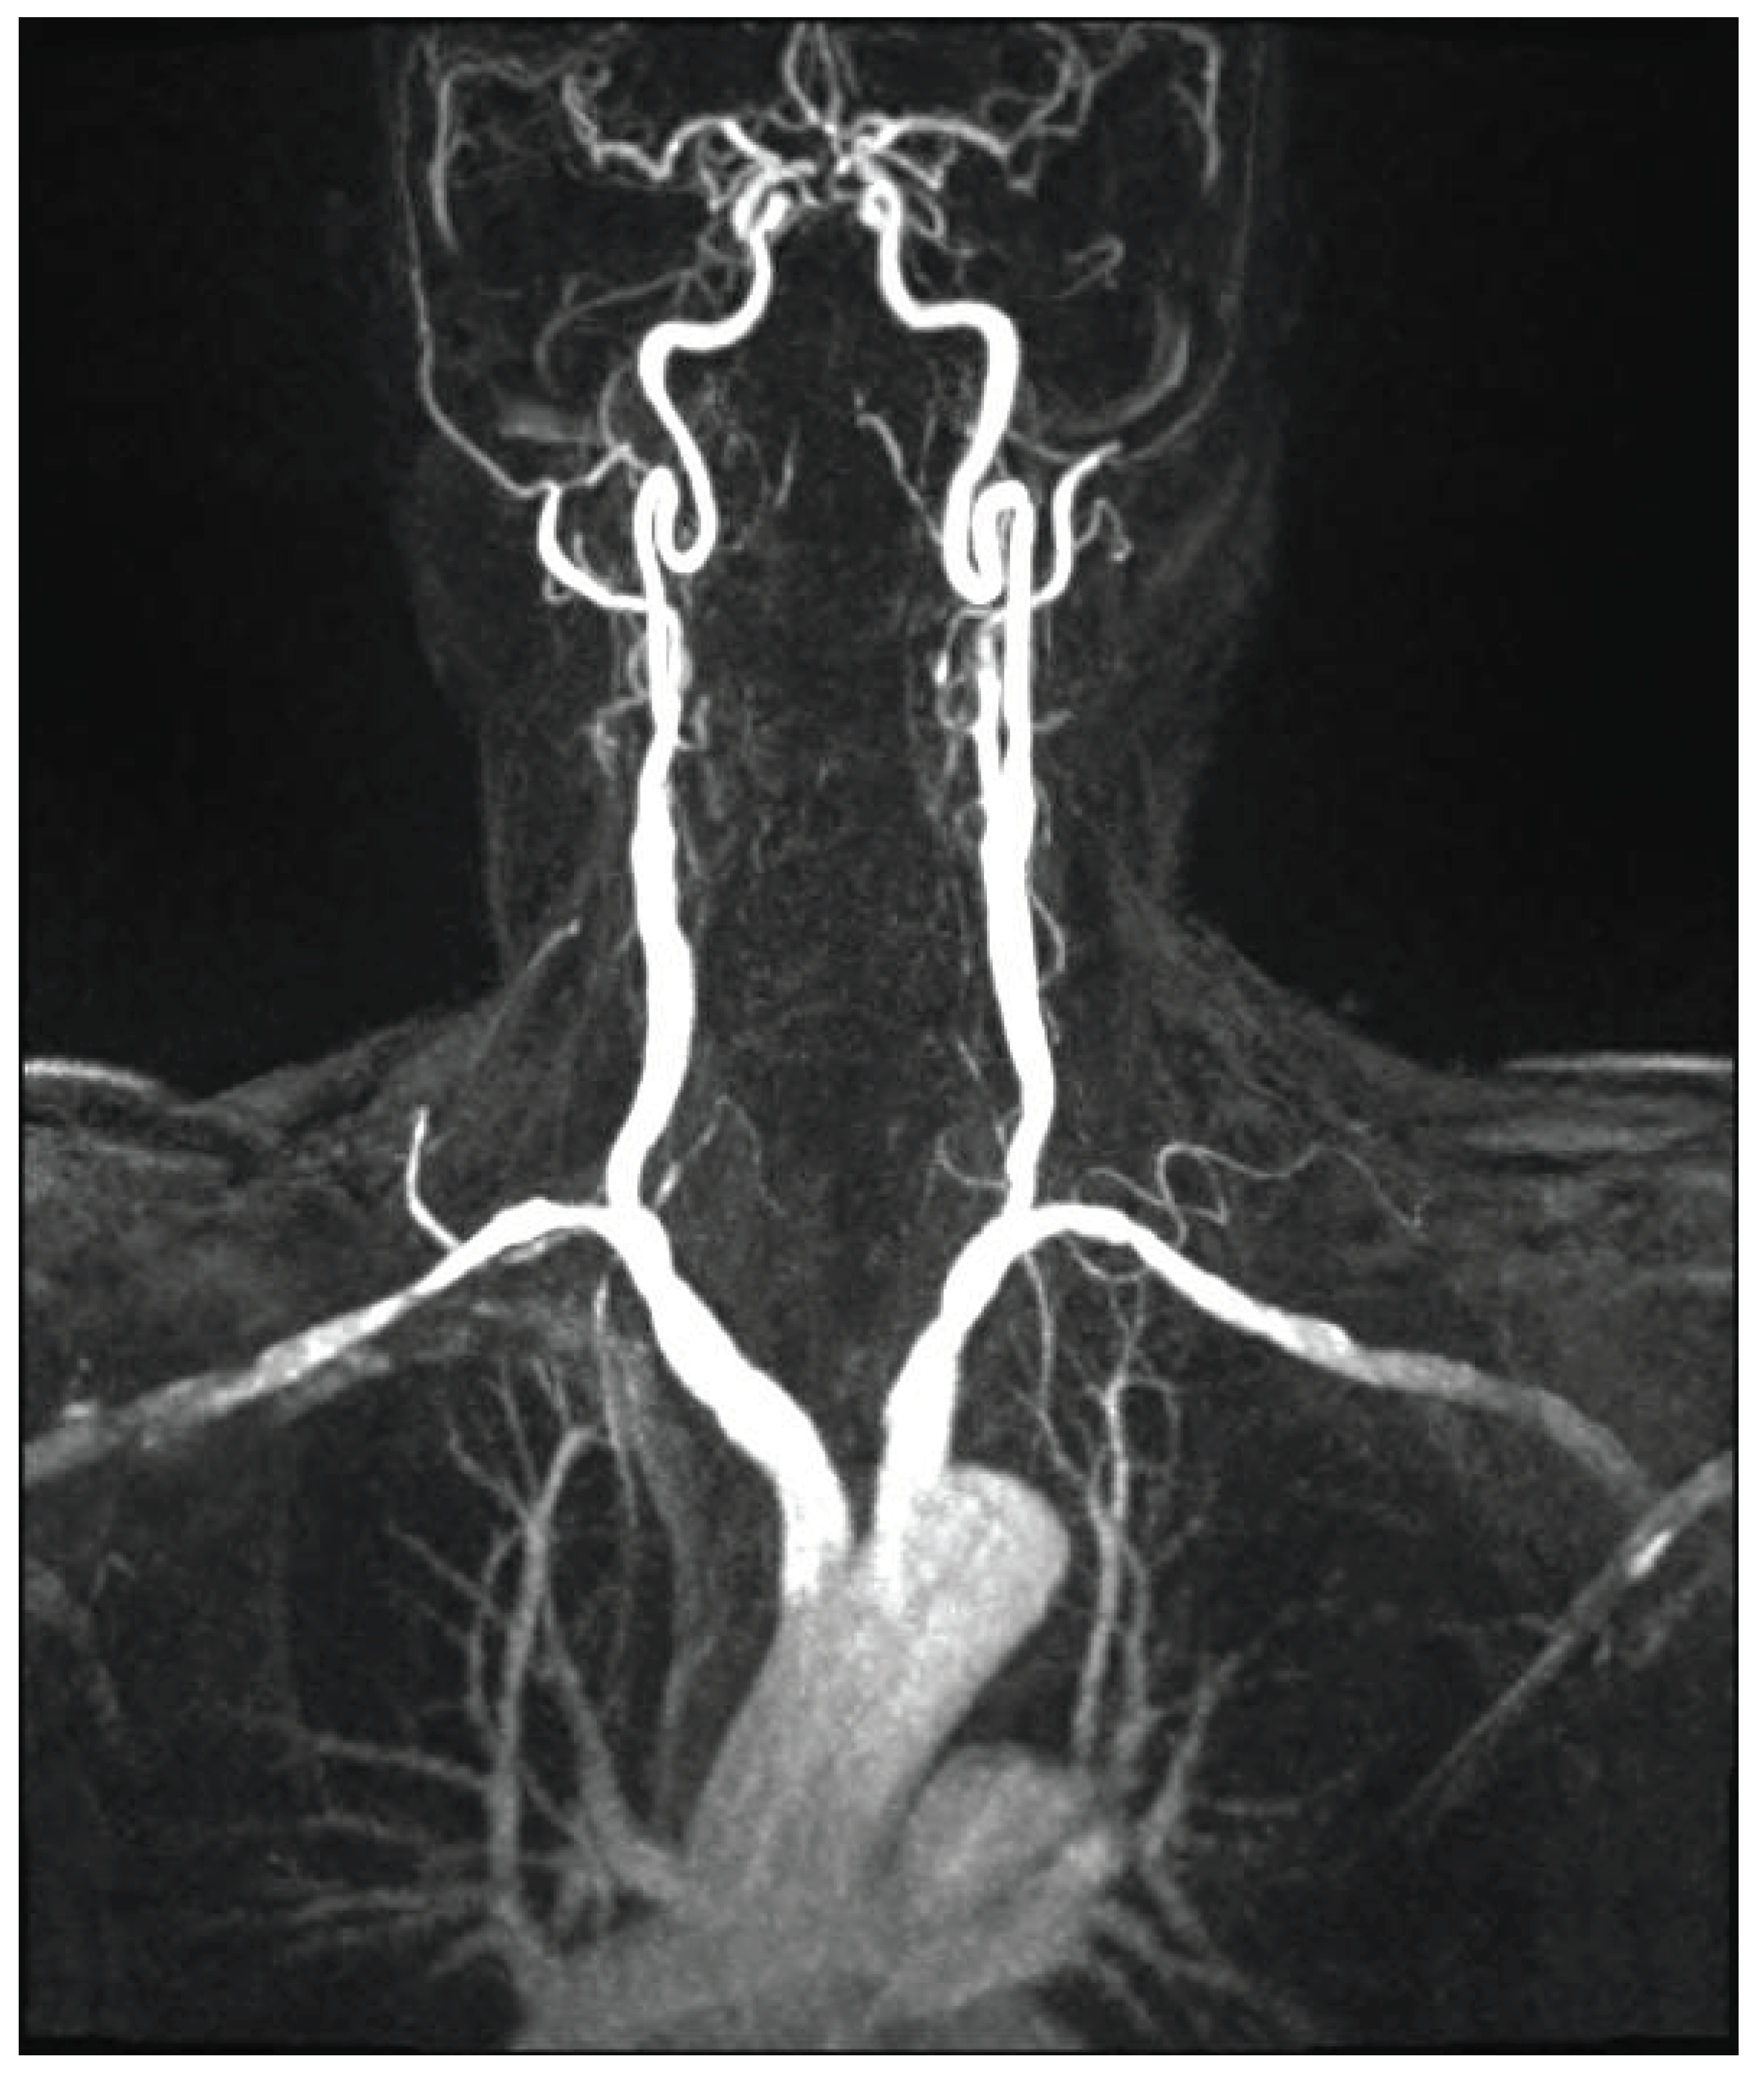

Since the advent of endovascular procedures, the histopathological classification has been replaced by an angiographic classification: focal or multifocal FMD. Multifocal FMD alternates areas of stenosis and dilation (“string of beads”) and is usually located in the mid and distal portion of the artery [147,148]. Recently, aneurysm, dissection, and arterial tortuosity have been included in the phenotype of FMD. However, a diagnosis of FAD cannot be established in the absence of focal or multifocal stenosis. Tortuosities can also be seen in the carotid, vertebral, and renal arteries. Tortuosity of the mid to distal portion of the internal carotid artery (ICA) may lead to an “S-curve”. The S curve is not specific for FMD, but its presence in individuals <70 years of age should alert the clinician [147]. Figure 1 and Figure 2.

Headaches are the most frequent, but non-specific symptoms (50-70% of patients with FMD) [147,151]. Pulsatile tintinnus may be associated with cervical artery dissection. The prevalence of cervical artery dissection and intracranial saccular aneurysm is higher among patients with FMD, with a higher rate of neurological complications (TIA, ischemic stroke, subarachnoid hemorrhage). Figure 3

The risk of long-term progression of FMD and the occurrence of aneurysm and dissection are not well-known [148]. CTA and MRA are the initial imaging modalities. Catheter-based angiography must be reserved for cases that may require intervention. Carotid DUS maybe useful for surveillance, but with some drawbacks: unsatisfactory access to vertebral and carotid arteries (especially the distal cervical portion of the ICA and intracranial arteries), no validated criteria for FMD [147]. Figure 4 and Figure 5